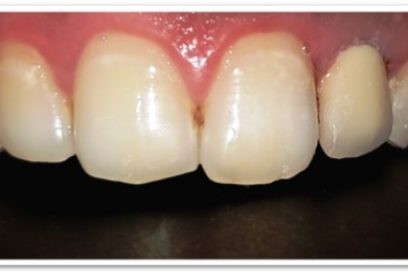

Patient Name: Rakesh Sinha

Tooth Involved : 11 12 21

Diagnosis : Caries Involving Enamel And Dentin Mesiocclusally

Treatment : Direct Composite Restorations Using Nanohybrid Composite

Before